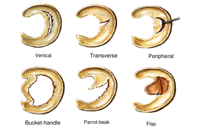

Menisci tear in different ways, depending on the mechanism of injury. Common types of tears include bucket handle, flap, and radial, complex.

Menisci tear in different ways, depending on the mechanism of injury. Common types of tears include bucket handle, flap, and radial, complex.